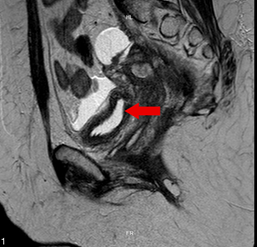

A 38-year-old female patient with a medical history of hypertension, glucose intolerance, ischemic stroke and a moderately differentiated cervical adenocarcinoma in remission. She underwent radiotherapy (total dose of 5040 cGy) and concurrent chemotherapy four years prior, followed by brachytherapy (650 cGy in four applications) approximately two years ago. One month prior to her visit, she had a diverting colostomy due to contained peritonitis associated with radiation-induced proctitis. She presented to the emergency department with acute abdominal pain, abdominal distension, multiple emetic episodes, and absence of bowel movements through the colostomy. Laboratory tests revealed leukocytosis and neutrophilia, with a negative C-reactive protein (CRP). An MRI of the abdomen and pelvis was performed, revealing a contained rectal perforation with an anterior collection in contact with the uterine wall, a second collection in the soft tissues of the anterior wall below the colostomy, radiation-induced proctitis and cystitis, severe adhesions, moderate dilation of small bowel loops without evidence of obstruction, accompanied by adjacent inflammatory changes, as well as free fluid in the lower abdomen and pelvis. Percutaneous drainage of the abdominal wall collection was carried out, and an internal-internal drain was placed for the pelvic collection via proctosigmoidoscopy, yielding a significant amount of milky fluid. Fluid analysis revealed triglyceride levels of 1068 mg/dL and negative cultures, confirming the diagnosis of chyloperitoneum. With a low-output drain, conservative management was initiated, including abdominal drainage and a low-fat diet as recommended by the nutrition team. After five days of observation, the patient showed symptom improvement and a decrease in drainage output. She was discharged with the drain in place and given dietary instructions. At a follow-up appointment one week later, the patient was asymptomatic, the drain was inactive, indicating full resolution, and it was removed without complications.

Figure 1 Contrast-enhanced MRI of the abdomen and pelvis in sagittal view shows the presence of a collection and free fluid in the abdominal cavity.